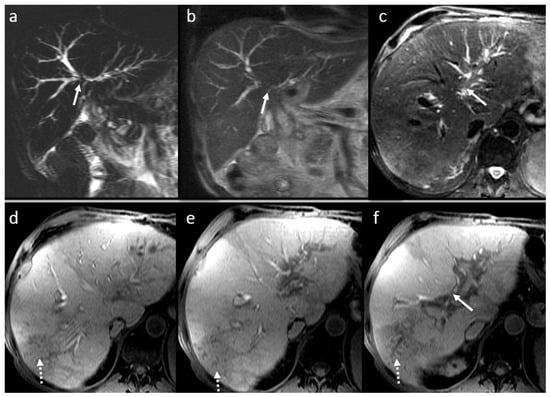

3.6. Secondary Cholangitis